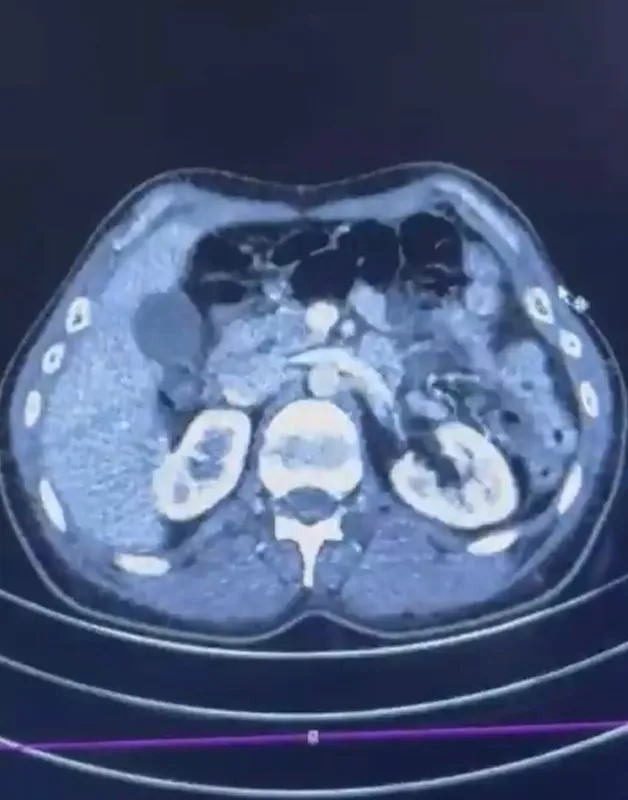

Kayseri İl Emniyet Müdürlüğü ekiplerince yapılan çalışmalarda İran’dan Türkiye’ye gelen şüphelilerin midesinde kapsül şeklinde yarım kilo uyuşturucu madde ele geçirildi.

Edinilen bilgiye göre Narkotik Suçlarla Mücadele Şube Müdürlüğü ekiplerince uluslararası uyuşturucu madde ticareti yapan kurye şahıslara yönelik gerçekleştirilen çalışmalarda, İran’dan Türkiye’ye uyuşturucu madde getirdiği tespit edilen şüpheli şahısların yakalanması amacıyla operasyon düzenlendi. Düzenlenen operasyonda; S.C., R.B.C. ve G.M. yakalandı. S.C. ve R.B.C.’nin Kayseri Şehir Hastanesi’nde yapılan iç beden muayenelerinde, mide kısımlarında bulunduğu tespit edilen 50 adet kapsül şeklinde toplam 554 gram uyuşturucu madde ele geçirildi. Şüpheliler gözaltına alınarak haklarında ’Uyuşturucu Madde Ticareti Yapmak’ işlem başlatıldı.